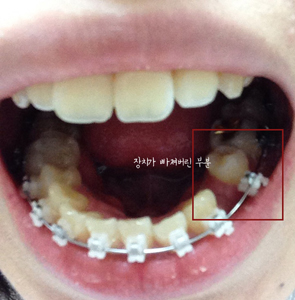

그런데 월치료날이 되기 전에 장치 하나가 탈락하는 바람에 중간에 한번더 치과에 다녀왔어요..

장치 탈락의 사건 전말은,,,

아침에 뜬눈으로 양치질을 부ㅡ아앙 하고있는데 나도 모르게 칫솔모를 씹은거에요 ,, 나름 조심조심 한다고 했는데

아직적응중인지라 우직했는데 칫솔모인데 괜찮겠지 했어요 ,, 근데 덜렁덜렁,,,, 장치가 떨어져버린겁니다. ㅜㅜ

힝 나의 소중한 킬본교정장치에 이런 스크레취가 일어나다니,, 장치가 떨어져버려서 그날은 점심,저녁도 조심조심 먹고

다음날 가서 바로 다시 장치 달으러갔어요,,

치과 도착후 장치를 살펴보시면서 말씀해주시기를 장치가 처음부터 붙여지기를 튼튼하게 붙여지지 않았다고 하시더라구요

그 얘기를 뭔가 안도의 마음이 ,,ㅋㅋㅋ 안그랬으면 앞으로 미음만 먹어야 할정도로 조심했어야 했을거에요,,

이렇게 장치 재부착을 완료하였습니다.